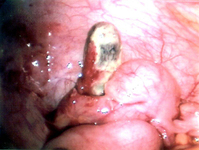

Apêndice necrótico

Do acervo de Dr. KuoJen Tsao; usado com permissão